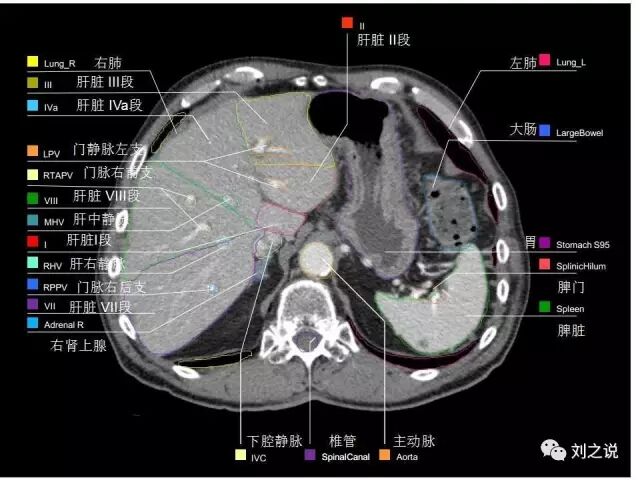

【解剖】高清实用 腹部CT断层

参考RTOG共识和3D-body解剖。